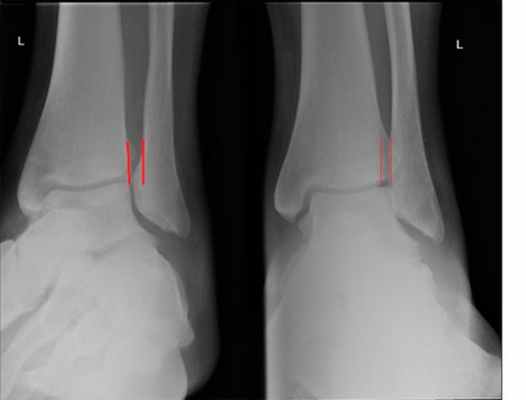

о Передне-задняя проекция: тени малоберцовой и большеберцовой костей перекрываются менее чем на 1 см:

- Данный признак не является надежным, поскольку на величину перекрытия влияет ротация голени

о Проекция суставной щели:

- Тени малоберцовой и большеберцовой костей перекрываются менее чем на 1 см:

Перекрытие может отсутствовать и в норме, если голень избыточно ротирована внутрь

Признак избыточной внутренней ротации голени: тень медиальной лодыжки накладывается на тень шейки таранной кости

- Расширение латерального свободного пространства:

В норме величина составляет 6 мм соответствует патологическим изменениям

о Если расширение синдесмоза в стандартных проекциях не визуализируется, его можно выявить при рентгенографии с нагрузкой (в положении пациента стоя или с наружной ротацией голени)

(Слева) При рентгенографии голеностопного сустава, выполненной в проекции суставной щели, определяются признаки повреждения синдесмоза: уменьшение глубины перекрытия теней большеберцовой и малоберцовой костей до менее чем 1 мм. Аналогичная картина может быть получена при избыточной внутренней ротации голени, однако при этом произошло бы наложение друг на друга теней медиальной лодыжки и тела таранной кости.

На рентгенограмме в переднее-задней проекции основными проявлениями недостаточности синдесмоза являются расширение вилки голеностопного сустава, расширение медиальной суставной щели и наклон таранной кости во фронтальной плоскости, травматическая эрозия плафона большеберцовой кости. Задний вывих малоберцовой кости в дистальной части голени виден, как заднее смещение малоберцовой кости относительно большеберцовой кости. Делают рентгенограммы с внутренней и наружной ротацией голени на которых имеется асимметрия суставной щели, расширение вилки голеностопного сустава, смещение наружной лодыжки назад и наклон таранной кости. Синдесмоз может оказаться поврежденным при отсутствии рентгенологических изменений. Самым информативным методом, который позволяет рассмотреть состояние отдельных связок, выявить дефект синдесмоза и определить соотношение костей голени является МРТ.